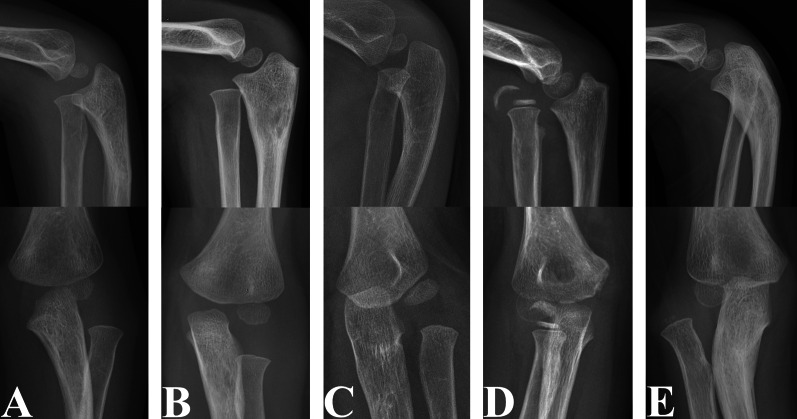

Materials and methods: We retrospectively reviewed 274 patients (mean age at injury: 5.82 ± 2.62 years) with UCMFs with all types of anterior (group A) and non-anterior (group B) radial head (RH) dislocations. Radiographs were used to assess the presence, size and bone density of HO. The risk factors evaluated included age at injury, sex, laterality, interval from injury to diagnosis, presence of radial or median nerve injury, immobilization of the fractured ulna after injury, direction of RH dislocation and distance of RH dislocation (DD-RH). The results were compared with 76 patient demographics-matched paediatric acute Monteggia fractures (PAMFs) undergoing surgery within 48 h after injury.

Results: The HO rate (13.1%) in children with UCMFs was significantly higher than that (0%) in children with PAMFs (P = 0.001). The incidence of HO (14.5%) in group A was significantly higher than that (0%) in group B (P = 0.032). Age at injury and DD-RH were confirmed as risk factors for HO in patients with UCMFs by both univariate and logistic regression analyses (P < 0.05). Receiver operating characteristic curve analysis and chi-squared analysis indicated that age at injury > 6.78 years and DD-RH < 1.59-fold of the narrowest radial neck width were the cut-off values for an increased HO rate in patients with UCMFs (P < 0.05). Increased age at injury (P = 0.041) and interval from injury to diagnosis (P = 0.006) were associated with high-bone density HO.

Conclusions: Patients with UCMFs with anterior RH dislocations, age at injury > 6.78 years, and DD-RH < 1.59-fold of the narrowest radial neck width were more likely to develop HO. The bone density of HO increases with age at injury and interval from injury to diagnosis. Timely RH reduction after acute injury may prevent HO.